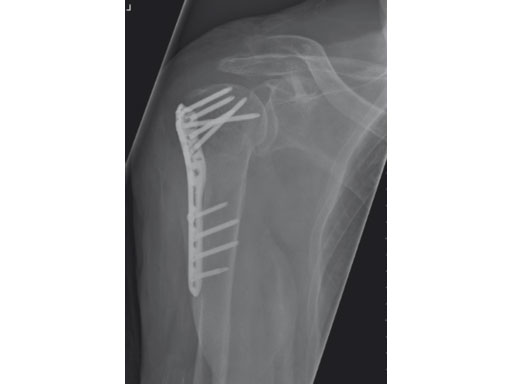

A 76-year-old woman suffered a low-energy fall at home.

Fig 1 Preoperative x-ray.

Fig 7 Postoperative result.